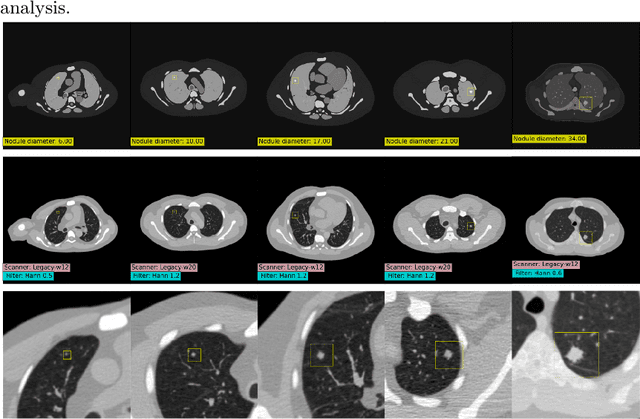

Abstract:AI models for lung cancer screening are limited by data scarcity, impacting generalizability and clinical applicability. Generative models address this issue but are constrained by training data variability. We introduce SYN-LUNGS, a framework for generating high-quality 3D CT images with detailed annotations. SYN-LUNGS integrates XCAT3 phantoms for digital twin generation, X-Lesions for nodule simulation (varying size, location, and appearance), and DukeSim for CT image formation with vendor and parameter variability. The dataset includes 3,072 nodule images from 1,044 simulated CT scans, with 512 lesions and 174 digital twins. Models trained on clinical + simulated data outperform clinical only models, achieving 10% improvement in detection, 2-9% in segmentation and classification, and enhanced synthesis.By incorporating anatomy-informed simulations, SYN-LUNGS provides a scalable approach for AI model development, particularly in rare disease representation and improving model reliability.